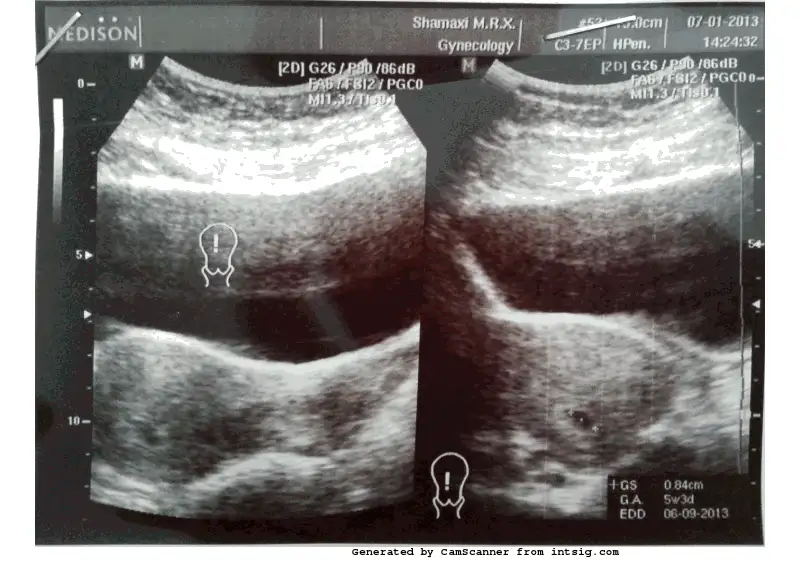

velhasıl bugün kontrole gittik. ultrasonla baktılar bebegimin kesesini gördük çok şükür. 5hafta 3 günlük hamileymişim. moralimizi bozan ise şu oldu. bebek tam yerinde degilmiş. biraz daha aşağıdaymış. ne çok aşağıdaymış nede tam yerindeymiş, tehlikesi varmış. kalp atışlarını da dinletmediler. tam bilemiyorum ama ekipmanları belkide yeterli değil dinletmeye. soru soruyorsun cevap vermiyorlar. verdikleri cevapta da tehlike tehlike diyorlar. sinirim asabım bozuldu. ben kendimi dinliyorum sanki herşey yolunda gibi hissediyorum. kafam karıştı açıkcası

size ultrason resmimi gönderiyorum. lütfen sizde kendinizinkini yollayın bir karşılaştıralım. yada anlayan varsa bana söylesin gercekten tehlikeli bir durumda mıyım? fitil, iğne, bir kaç tane de hap yazdılar. ben almadım hiçbirini. önce Türkiyedeki doktoruma mail attım sonucları. onun degerlendirmesini bekleyecegim. ben bebeğimi istiyorum kızlar. onu şimdiden çok seviyorum. inşallah herşey yoluna girer herşey güzel ve hayırlı olur hepimiz için.

Eki Görüntüle 597941